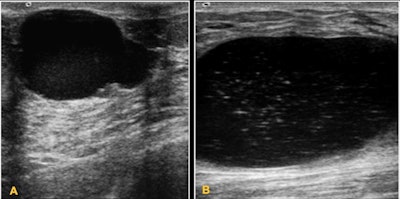

- Some benign lesions tend to grow rapidly, causing huge masses.

- In children, when necessary, the initially recommended imaging technique is breast ultrasound.